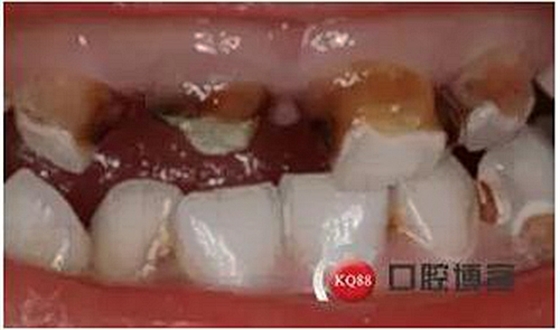

患兒 女 4歲

主訴:上前牙齲壞發(fā)黑數(shù)月余

現(xiàn)病史:患兒家長代述患兒上前牙齲壞發(fā)黑數(shù)月余,速度發(fā)展快,未處置,今來院就診。

檢查:51,殘冠,牙合面齲壞達牙本質(zhì)深層,冷熱診無反應,探診(-),叩痛(+),唇側牙齦見瘺管,X線示根尖部見大面積低密度陰影;52,61,62頸部環(huán)狀齲壞達牙本質(zhì)深層,冷熱診敏感,探診(+),叩痛(-),X線示齲壞低密度陰影與髓腔連通。